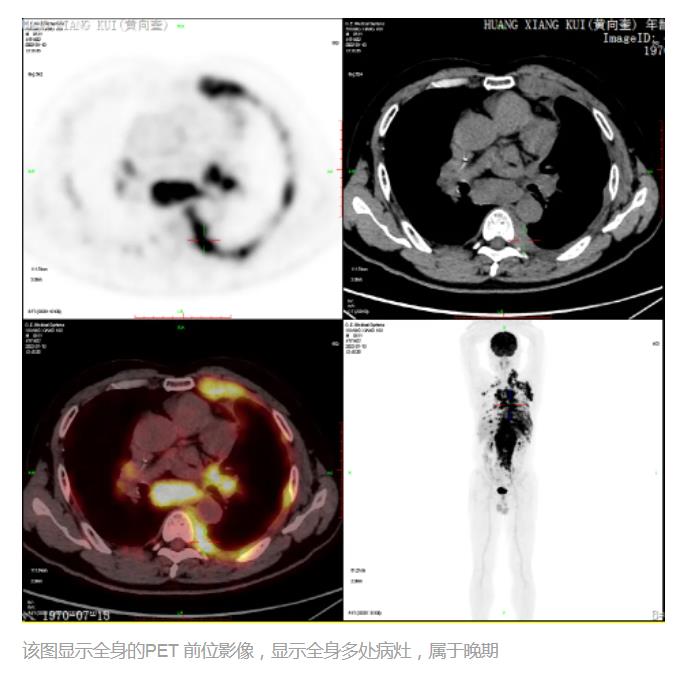

战胜血液系统癌症的新“武器”CAR-T细胞疗法